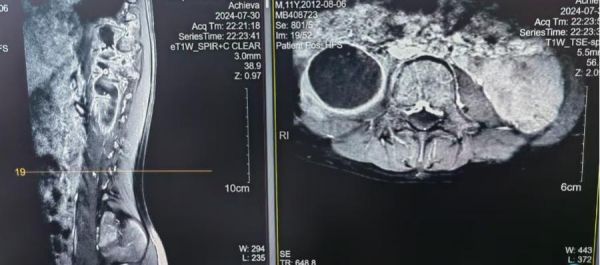

直到今年7月初,成成偶尔觉得腰痛。家里人带他到浙大儿院检查后,被发现脊髓受压、腰大肌巨大脓肿,而造成这一切的罪魁祸首是骨结核。

随后,浙大儿院感染科、浙江省儿童结核病艾滋病临床诊治中心针对成成的情况,完善了进一步的检查,为孩子制定了合适的诊疗方案。

怎么还会有骨结核?感染科结核病专科门诊医生李嫣表示,对于结核病来说,除了肺结核之外,还有结核性胸膜炎、结核性脑膜炎、纵膈淋巴结核、肺门淋巴结结核、骨结核等各种全身结核感染的情况。对于一些结核潜伏时间较长的患儿来说,身上很可能出现多种结核感染的严重情况。因此,及时筛查出这些患儿非常重要。